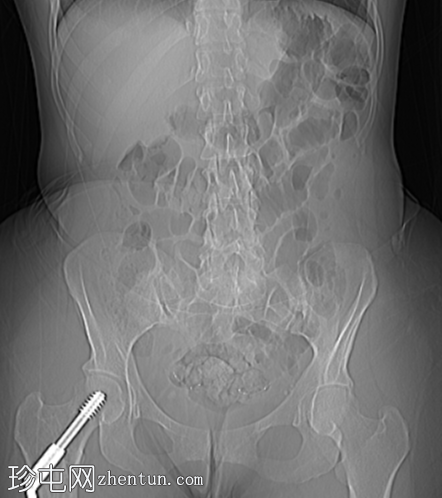

定位扫描

肝内和肝外胆管中度扩张,胆总管(13 mm)内可见一小块边缘不透光结石(8 mm)。

双侧输卵管结扎术。

右侧股骨动力髋螺钉。